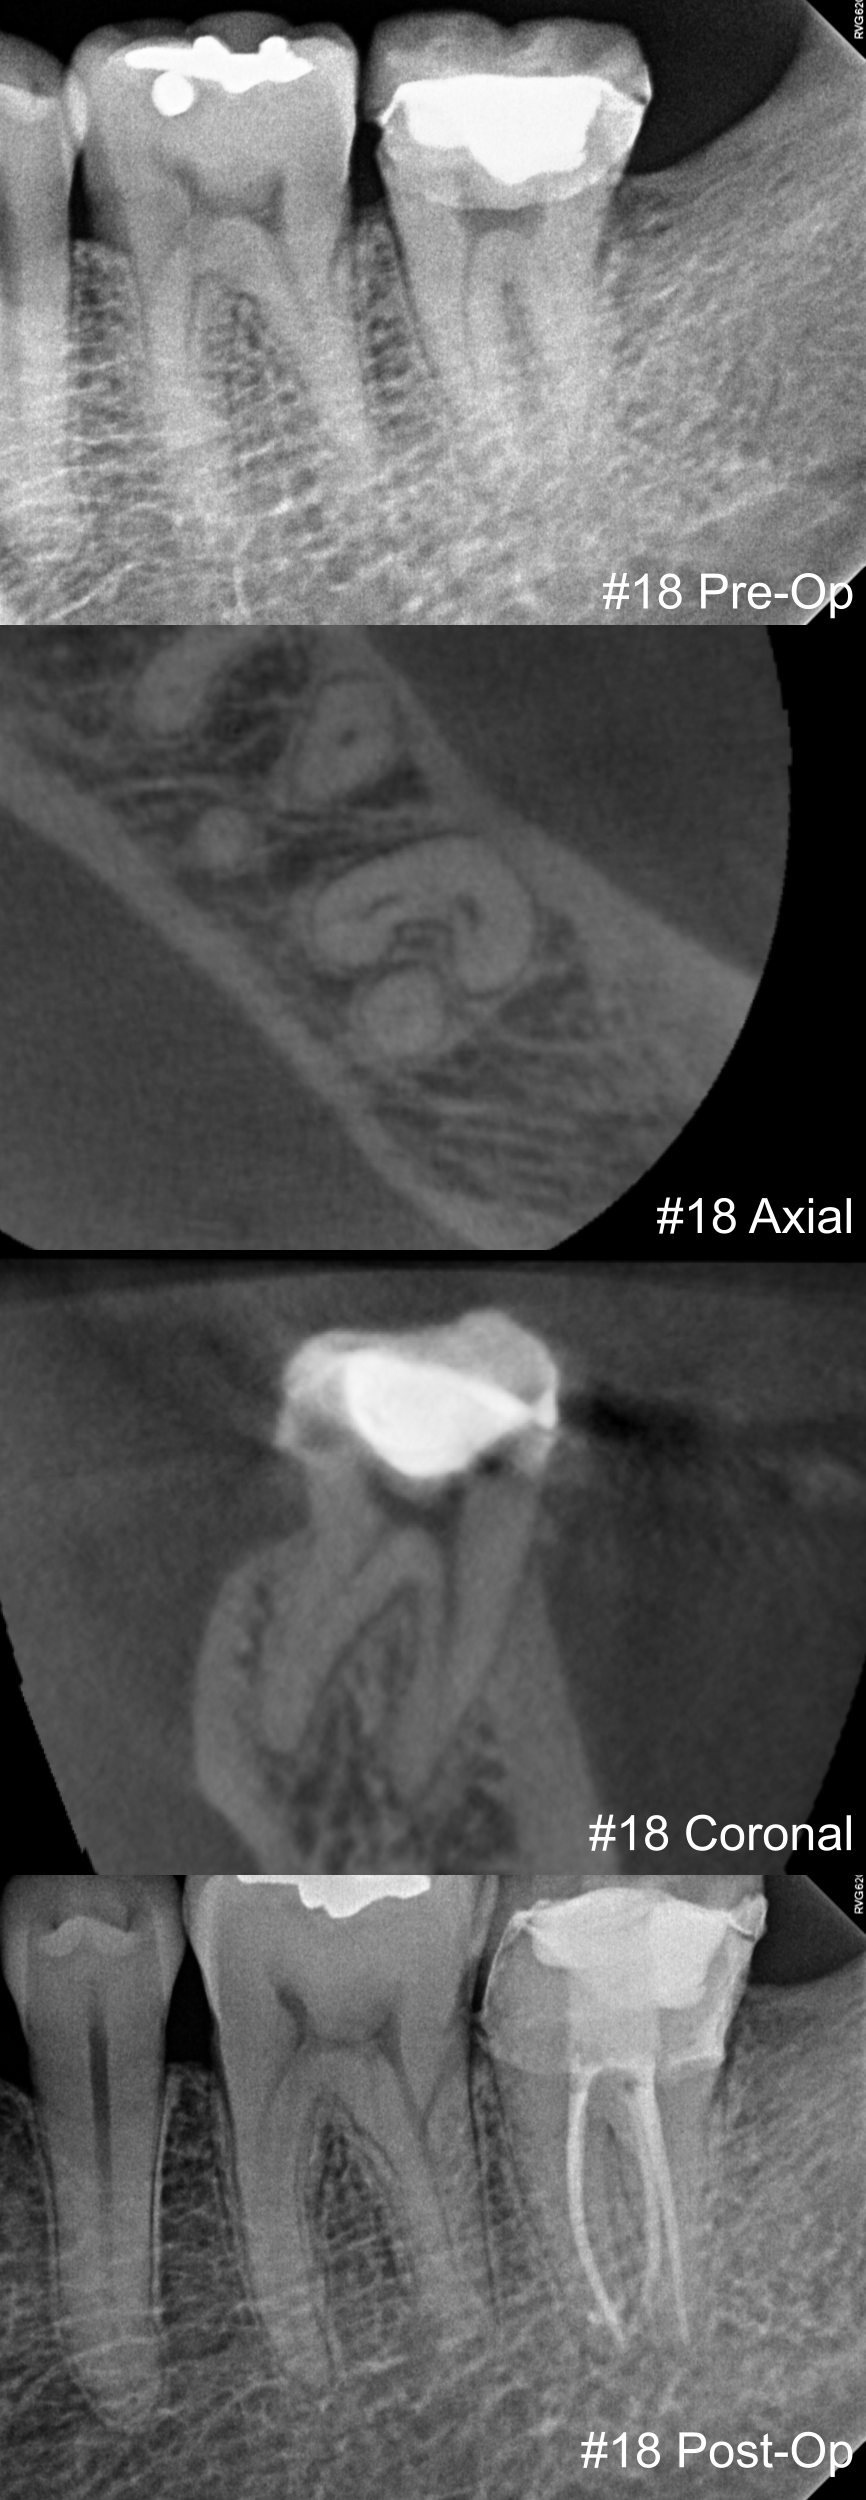

View fullsize